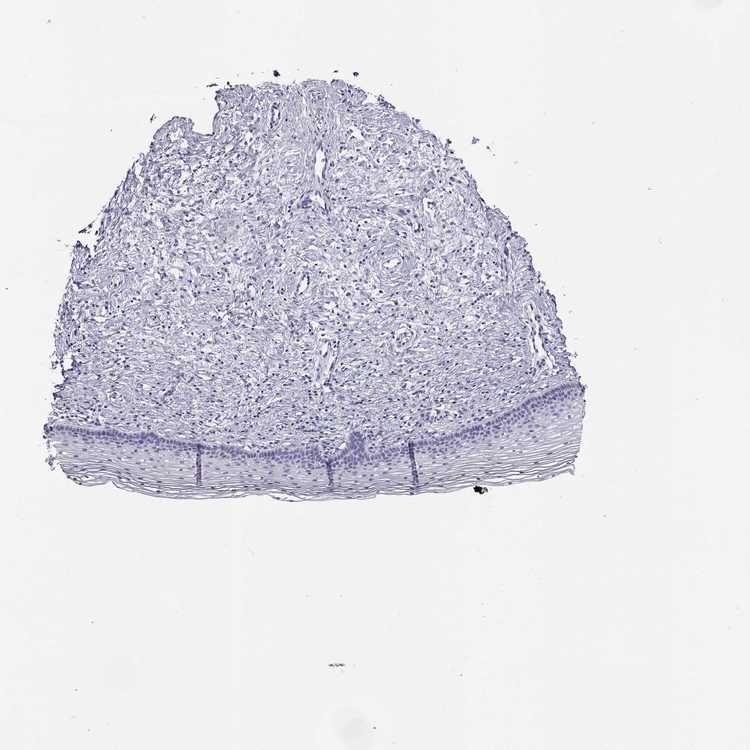

CERVIX - Antibody stainingi

Antibody staining in the annotated cell types in the current human tissue is reported as not detected, low, medium, or high, based on conventional immunohistochemistry profiling in selected tissues. This score is based on the combination of the staining intensity and fraction of stained cells.

Each image is clickable and will lead to virtual microscopy that enables deeper exploration of all samples and also displays staining intensity scores, fraction scores and subcellular localization as well as patient and tissue information for each sample.

Antibody HPA057790

Glandular cells Not detected

Squamous epithelial cells Not detected